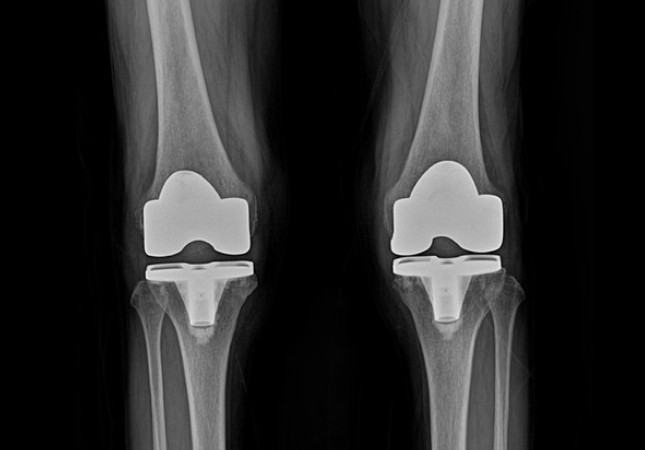

퇴행성 관절염의 말기 단계에서는 관절의 경직이 발생하여 무릎이 완전히 펴지지 않거나 구부릴 때 제한이 생길 수 있으며, 걷는 동안 통증이 극심해질 수 있습니다. 이로 인해 밤에 다리를 움직이지 않아도 통증이 심해져 잠을 설치는 경우가 많습니다. 연골이 완전히 닳아 없어지는 말기에는 인공관절 수술이 필요합니다. 이 수술은 손상된 연골을 제거하고 그 자리에 인공으로 제작된 관절을 삽입하는 과정을 포함합니다.